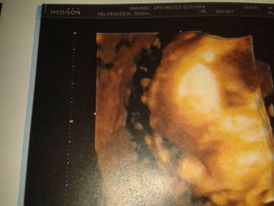

ECO 3D DE MI BEBEmarlysv (25)in #spanish • 8 years ago AMIGOS Y COMUNIDAD STEEMIT, AQUI LES MUESTRO UNA FOTO DEL ECO 3D DE MI BEBE, YA ESTA FORMADITO GRACIAS A DIOS. #ingles #cervante #photo

Gracias, si de verdad es impresionante como puedes ver como es tu bebe si aun haber nacido.